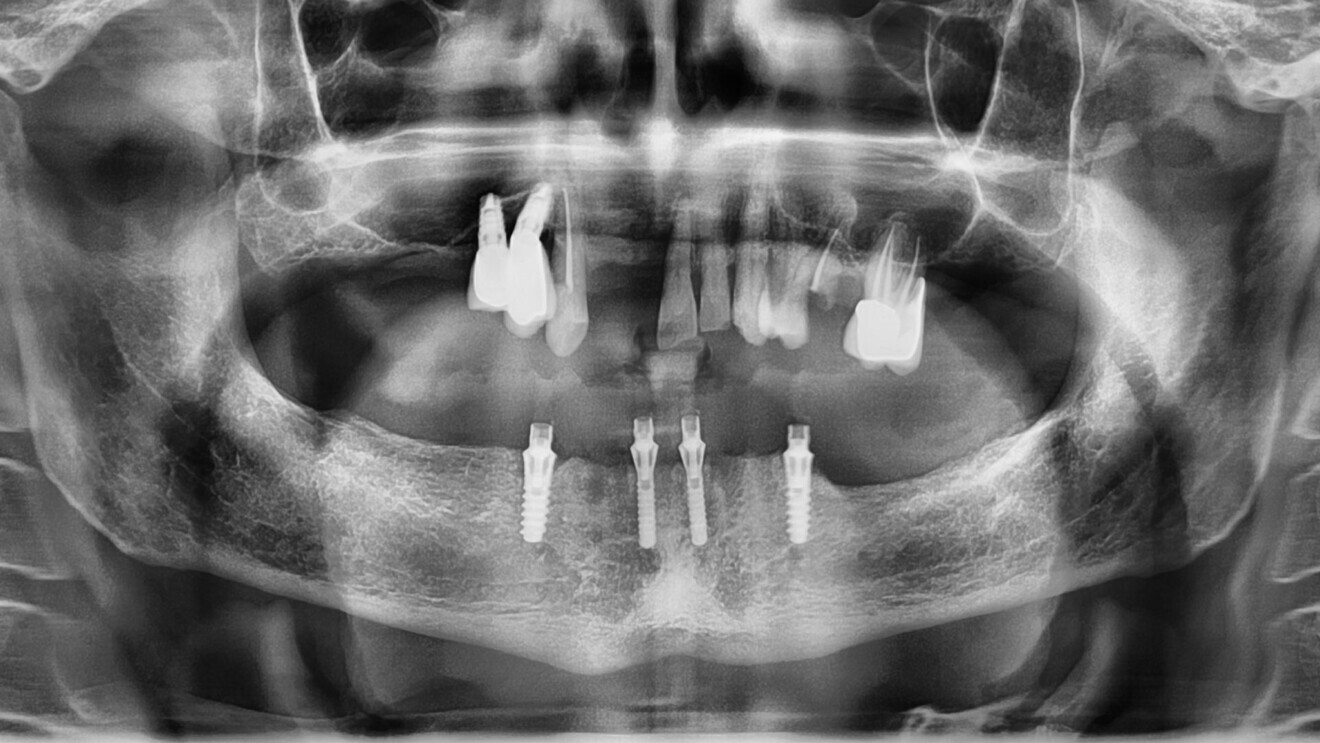

La radio panoramique (Fig. 15), quant à elle, nous montre une uniformité dans la répartition de la position des implants, ainsi qu’une connexion pilier conique-implant de type cône morse du All-on-4 au maxillaire, ce qui assure une étanchéité nécessaire à des implants posés en position infra-osseuse. Nous observons un cas classique de réhabilitation par quatre implants verticaux à la mandibule.